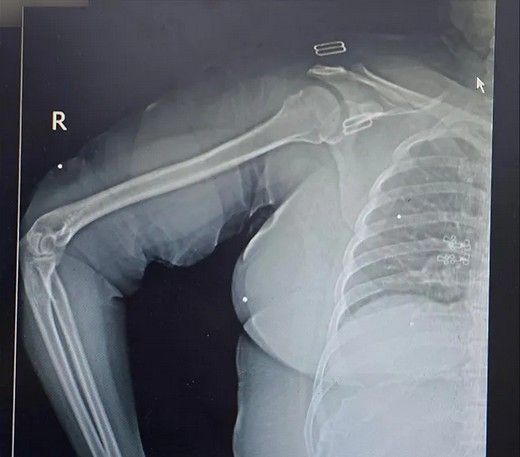

استخوانهای خردشده دست و پا

دست و پای معترضان در شهر رشت نیز از شلیکهای ماموران جمهوری اسلامی در امان نبودهاند. تصاویر رادیوگرافی نشان میدهد بسیاری از معترضان در ناحیه دست و پا هدف تیرهای ساچمهای قرار گرفتهاند، شدت آسیب در برخی موارد تا حدی بوده که استخوان ساعد، ساق یا مچ پا خرد شدهاند. همچنین موارد متعددی از شکستگی در دست و پای معترضان بدون شلیک گلوله نیز دیده میشود.

یکی از شدیدترین جراحات متعلق به زنی است که نه تنها کتف، بازو، ران و ناحیه تناسلی او هدف تیر ساچمهای قرار گرفته است، بلکه استخوان ران او نیز با اصابت گلوله جنگی خرد شده است. در تصاویر مشخص است که از فیکساتور برای درمان این مجروح استفاده شده است.

استخوانهای خردشده دست و پادست و پای معترضان در شهر رشت نیز از شلیکهای ماموران جمهوری اسلامی در امان نبودهاند. تصاویر رادیوگرافی نشان میدهد بسیاری از معترضان در ناحیه دست و پا هدف تیرهای ساچمهای قرار گرفتهاند، شدت آسیب در برخی موارد تا حدی بوده که استخوان ساعد، ساق یا مچ پا خرد شدهاند. همچنین موارد متعددی از شکستگی در دست و پای معترضان بدون شلیک گلوله نیز دیده میشود.